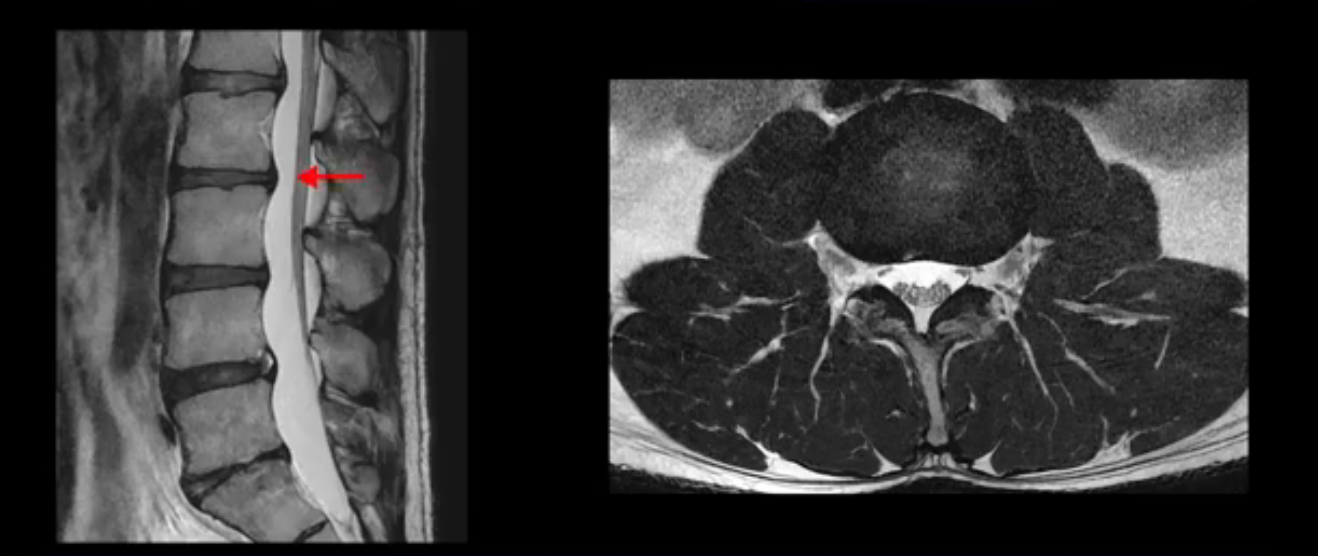

5번 1번 역시 가운데로 디스크 조금 밀려 나와있지만 신경 공간 넓이는 아주 넓어서 신경 눌림 있을 거라고 예상이 안됩니다.

추간공도 보시다시피 왼쪽, 오른쪽 전부 다 매우 넓어서 신경이 눌릴만한 부분이 전혀 보이지 않습니다.

앞서 1번 2번, 4번 5번, 5번 1번의 디스크가 찢어지고 조금 밀려 나온 게 최근에 찢어진 게 아니고 오래된 걸로 보인다고 말씀 드렸죠. 왜 그럴까요? 만약 급성으로 찢어진 것이라면 아주 심한 디스크성 통증이 있겠죠. 기침이나 재채기를 하면 심하게 아프고 허리를 조금만 구부리거나 비틀면 아주 날카로운 통증들이 생길 겁니다. 그런데 이분은 이런 증상이 전혀 아닙니다. 또 디스크의 밀려나온 정도도 전혀 심하지 않기 때문에 이분이 가지고 계신 양쪽 다리 저림, 특히 이분은 누워있을 때도 양쪽 발이 발가락까지 쑤신다고 하는데 이정도 디스크 때문에 그런 증상은 생길 수가 없는 겁니다. 이처럼 이분의 가벼운 디스크 탈출은 이미 오래 전에 진행되었고 섬유륜 자체는 이미 아문 상태인데도 디스크내장증을 진단받은 환자들 중에는 본인이 섬유륜 파열 환자라고 끝까지 믿는 분들이 많습니다. 다시 말하지만 디스크내장증이라는 진단을 받은 환자들을 보면 거의 전부 다 섬유륜 파열 증상이 아닙니다. 증상이 완전히 다릅니다. 진단이 애초에 잘못되면 어떤 치료를 받아도 좋아질 수 없습니다.